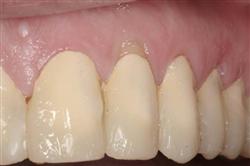

Normally gum tissue surrounds and protects the delicate roots of your teeth. Exposed tooth roots are prone to tooth decay, root canals, discoloration and actual jawbone loss. All of this can lead to tooth loss in advanced cases.

Functional Soft Tissue Grafting replaces the missing gum tissue and protects your teeth. For this reason, soft tissue grafting may be recommended even for back teeth.

Cosmetic Soft Tissue Grafting

In addition to the functional problems previously mentioned, receding gums can look unsightly.

Longer looking teeth and exposed tooth roots give an "old" appearance to your smile. Some people cover their mouths when they smile for this very reason.

Cosmetic Soft Tissue Grafting can add a new youthful appearance to your smile. In your initial consultation with Dr. Hoidal, he will thoroughly explain what can be achieved in your particular case.